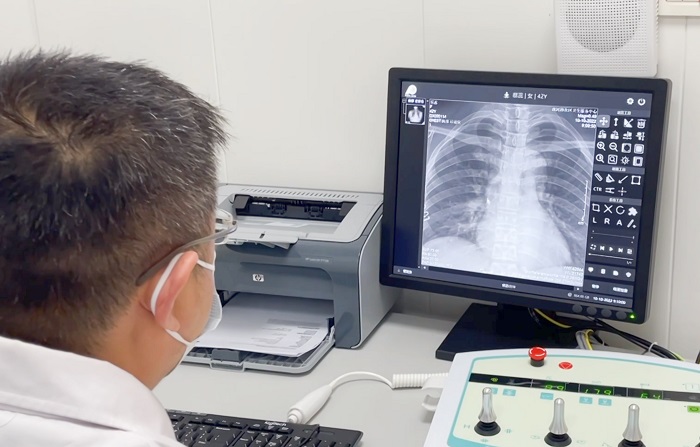

X射線機(jī)作為最基礎(chǔ)、最常用的影像檢查設(shè)備,也是體檢科必備的設(shè)備之一。體檢科人流量大,對(duì)于拍片設(shè)備的要求相對(duì)更加嚴(yán)格。普利德多功能動(dòng)態(tài)平板DRF自進(jìn)入市場(chǎng)以來,以其性能穩(wěn)定、圖像清晰、快速成像等多種優(yōu)勢(shì)受到各級(jí)醫(yī)療機(jī)構(gòu)體檢科的青睞,尤其在應(yīng)對(duì)大規(guī)模、高流通量檢查中表現(xiàn)優(yōu)異!

不同于常規(guī)DR只能進(jìn)行平片攝影檢查,普利德多功能動(dòng)態(tài)平板DRF動(dòng)靜兼?zhèn)?,可?shí)現(xiàn)大幅面低劑量透視檢查,在日常的體檢工作中,比如胸部及肺部檢查,可對(duì)重疊部位病變進(jìn)行可視化觀察及多角度旋轉(zhuǎn)體位,發(fā)現(xiàn)疑似病灶可瞬時(shí)完成高清點(diǎn)片,顯著提高診斷的準(zhǔn)確性。

動(dòng)態(tài)采集幀率最高可達(dá)30幀/s,影像細(xì)膩流暢,便于醫(yī)生對(duì)細(xì)微病變的觀察。17×17英寸大幅面成像,在透視過程中能對(duì)患者的胸部腹部等部位實(shí)現(xiàn)大范圍覆蓋,便于從整體上觀察組織信息,更加全面且精準(zhǔn)的捕捉病灶。